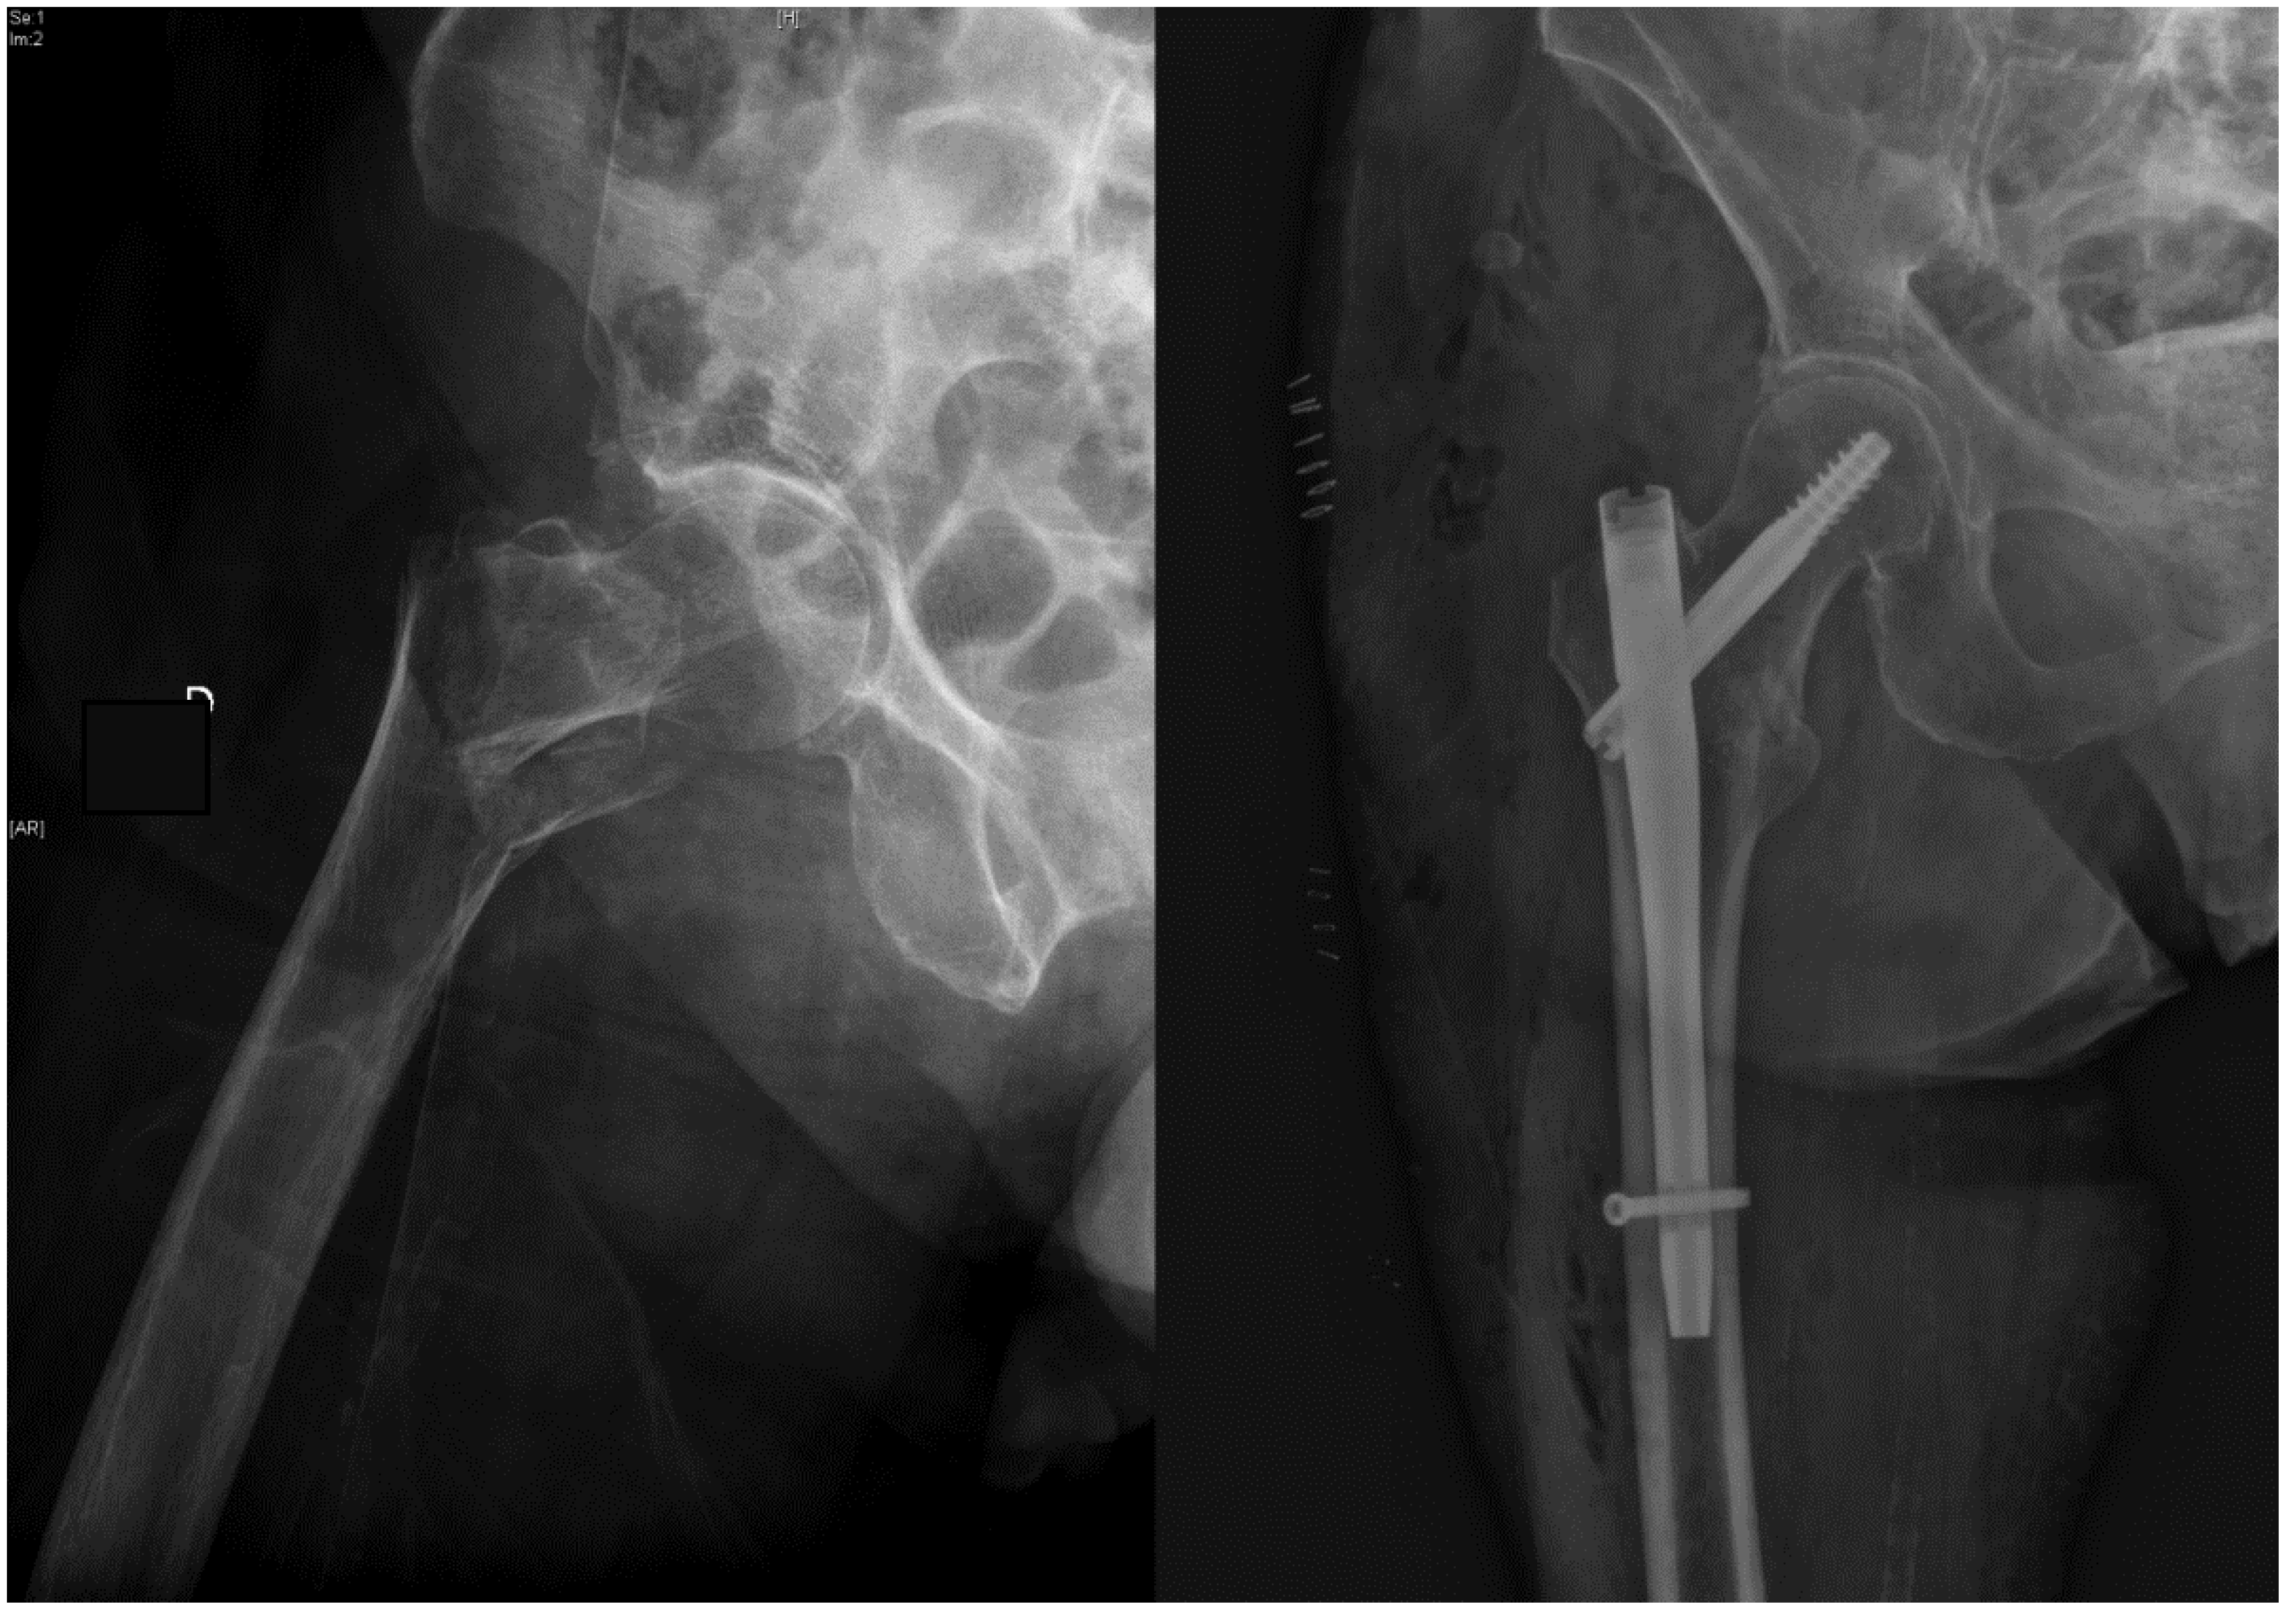

Treatment of Trochanteric Hip Fractures with Cephalomedullary Nails: Single Head Screw vs. Dual Integrated Compression Screw Systems

| Reoperations in the follow-up period after surgery, n (%) | 17 & (4.4%) | 6 (2.3%) | 11 & (8.8%) | 0.008 |

| Reoperation required, rates at 1.5 Years Following Surgery *, % | 5.8% | 1.9% | 13.3% | 0.009 |

| InterTAN vs. Gamma3 nail | - | - | 3.6 [1.3–10.5] | 0.017 |